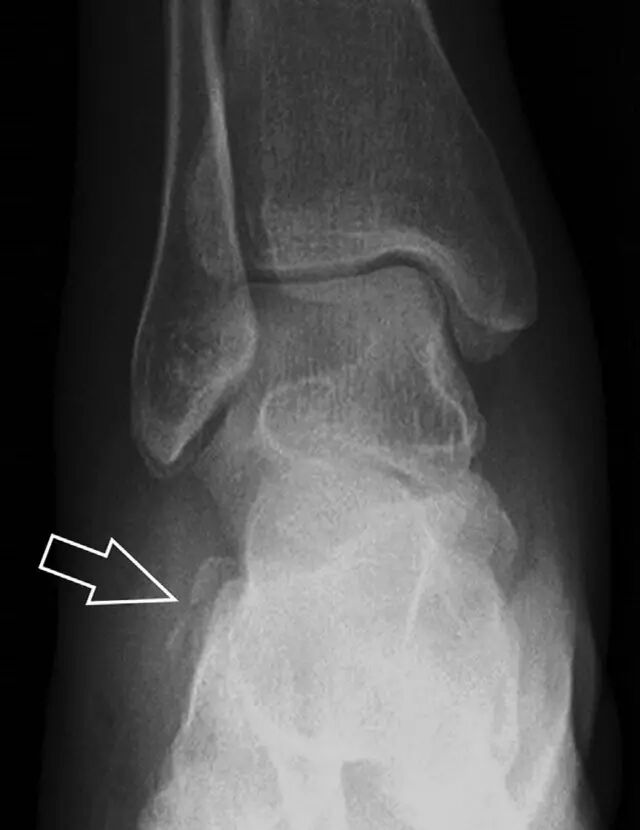

距骨外侧突骨折常因踝外翻背屈时,跟骨上外侧面撞击距骨外侧突下缘导致,或偶尔由踝内翻引起,被称为「滑雪板者骨折」。这种骨折只能在踝关节正位片上发现,而且外踝远端表面软组织肿胀往往是一个重要线索(图 4)。

图 4 距骨外侧突骨折。A 正位片示内翻损伤所致的距骨外侧突撕脱性骨折(箭头);B 另一位患者,踝外翻损伤导致典型的「滑雪板者骨折」,X 片上可见一较大的三角形骨折块(方框);C 第二位患者的 MRI 矢状位 T1 加权像示横行骨折(箭头)